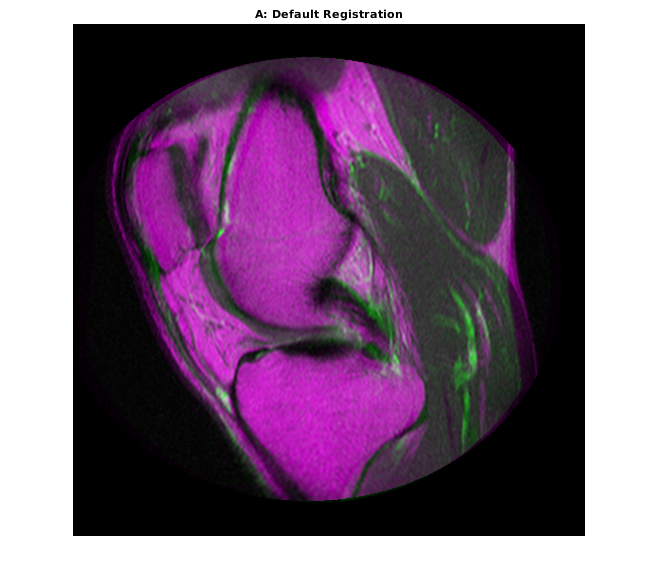

movingRegisteredDefault = imregister(moving,fixed,'affine',optimizer,metric); imshowpair(movingRegisteredDefault,fixed) title('A: Default Registration')

Первичная регистрация не очень хороша. Существуют все еще значительные области плохого выравнивания, особенно вдоль правого края. Попытайтесь улучшить регистрацию путем корректировки оптимизатора и метрических свойств настройки.